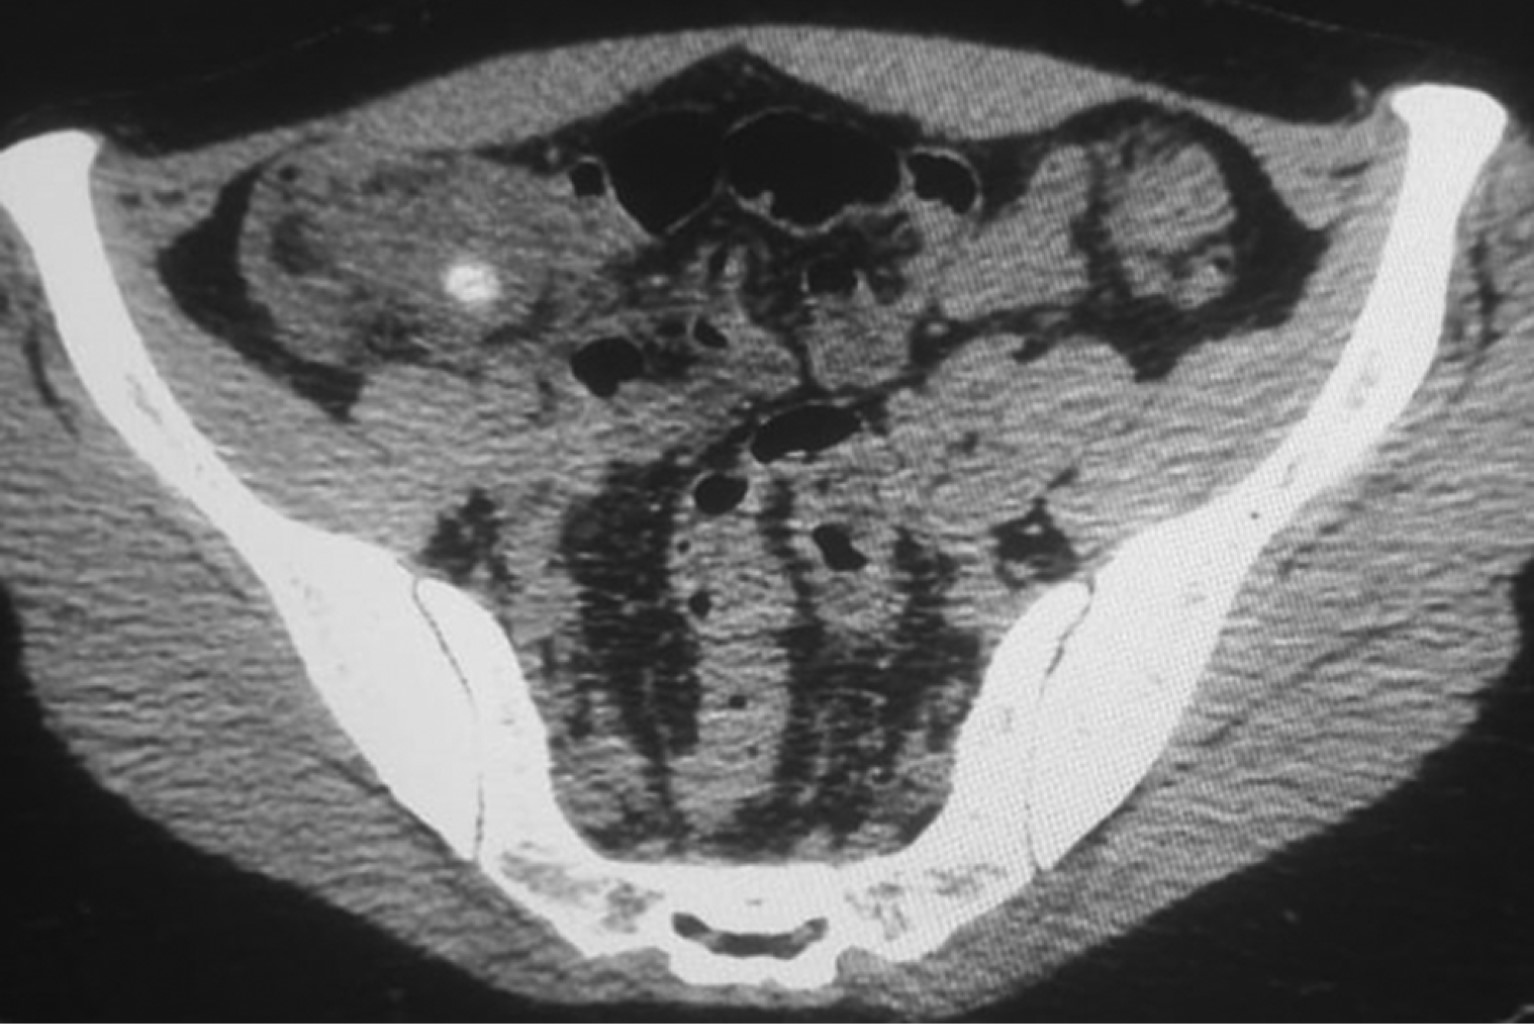

Paciente femenino de 36 años, con antecedentes familiares de diabetes mellitus por parte de su abuela materna. Niega tabaquismo, etilismo u otras toxicomanías. Antecedentes personales de enfermedad celíaca de reciente diagnóstico y apendicectomía 20 años antes. Presenta dolor abdominal difuso que se localiza en hipocondrio derecho con irradiación a región dorsal derecha acompañado de fiebre y evacuaciones disminuidas en consistencia, inicialmente tratada con paracetamol y antibióticos de amplio espectro, sin presentar mejoría, por lo que es revalorada. A la exploración física se observa paciente con taquicardia, febril, ligeramente deshidratada, con datos de irritación peritoneal (rebote en cuadrante inferior derecho del abdomen). En la tomografía de abdomen se observa una imagen compatible con apendicitis de muñón, con fecalito hacia la punta (Figura 1). Se reporta por imagenología: "Proceso inflamatorio a nivel de la fosa iliaca derecha sugiere como primera posibilidad diagnóstica apendicitis de muñón con presencia de plastrón. Imagen que sugiere apendicolito. Adenopatías pericecales y perineales de apariencia inflamatoria". La paciente pasa a laparoscopia diagnóstica donde se encuentra plastrón inflamatorio en región de ciego que no se puede disecar de manera adecuada (Figura 2A y B ). Se realiza conversión a laparotomía, encontrando muñón apendicular largo, abscedado y con afectación de válvula ileocecal, por lo que se realiza ileocequectomía y anastomosis latero lateral mecánica con engrapadora lineal cortante. El reporte de patología indica "hallazgos compatibles con apendicitis aguda". La paciente evoluciona adecuadamente en el postoperatorio.

Figura 1